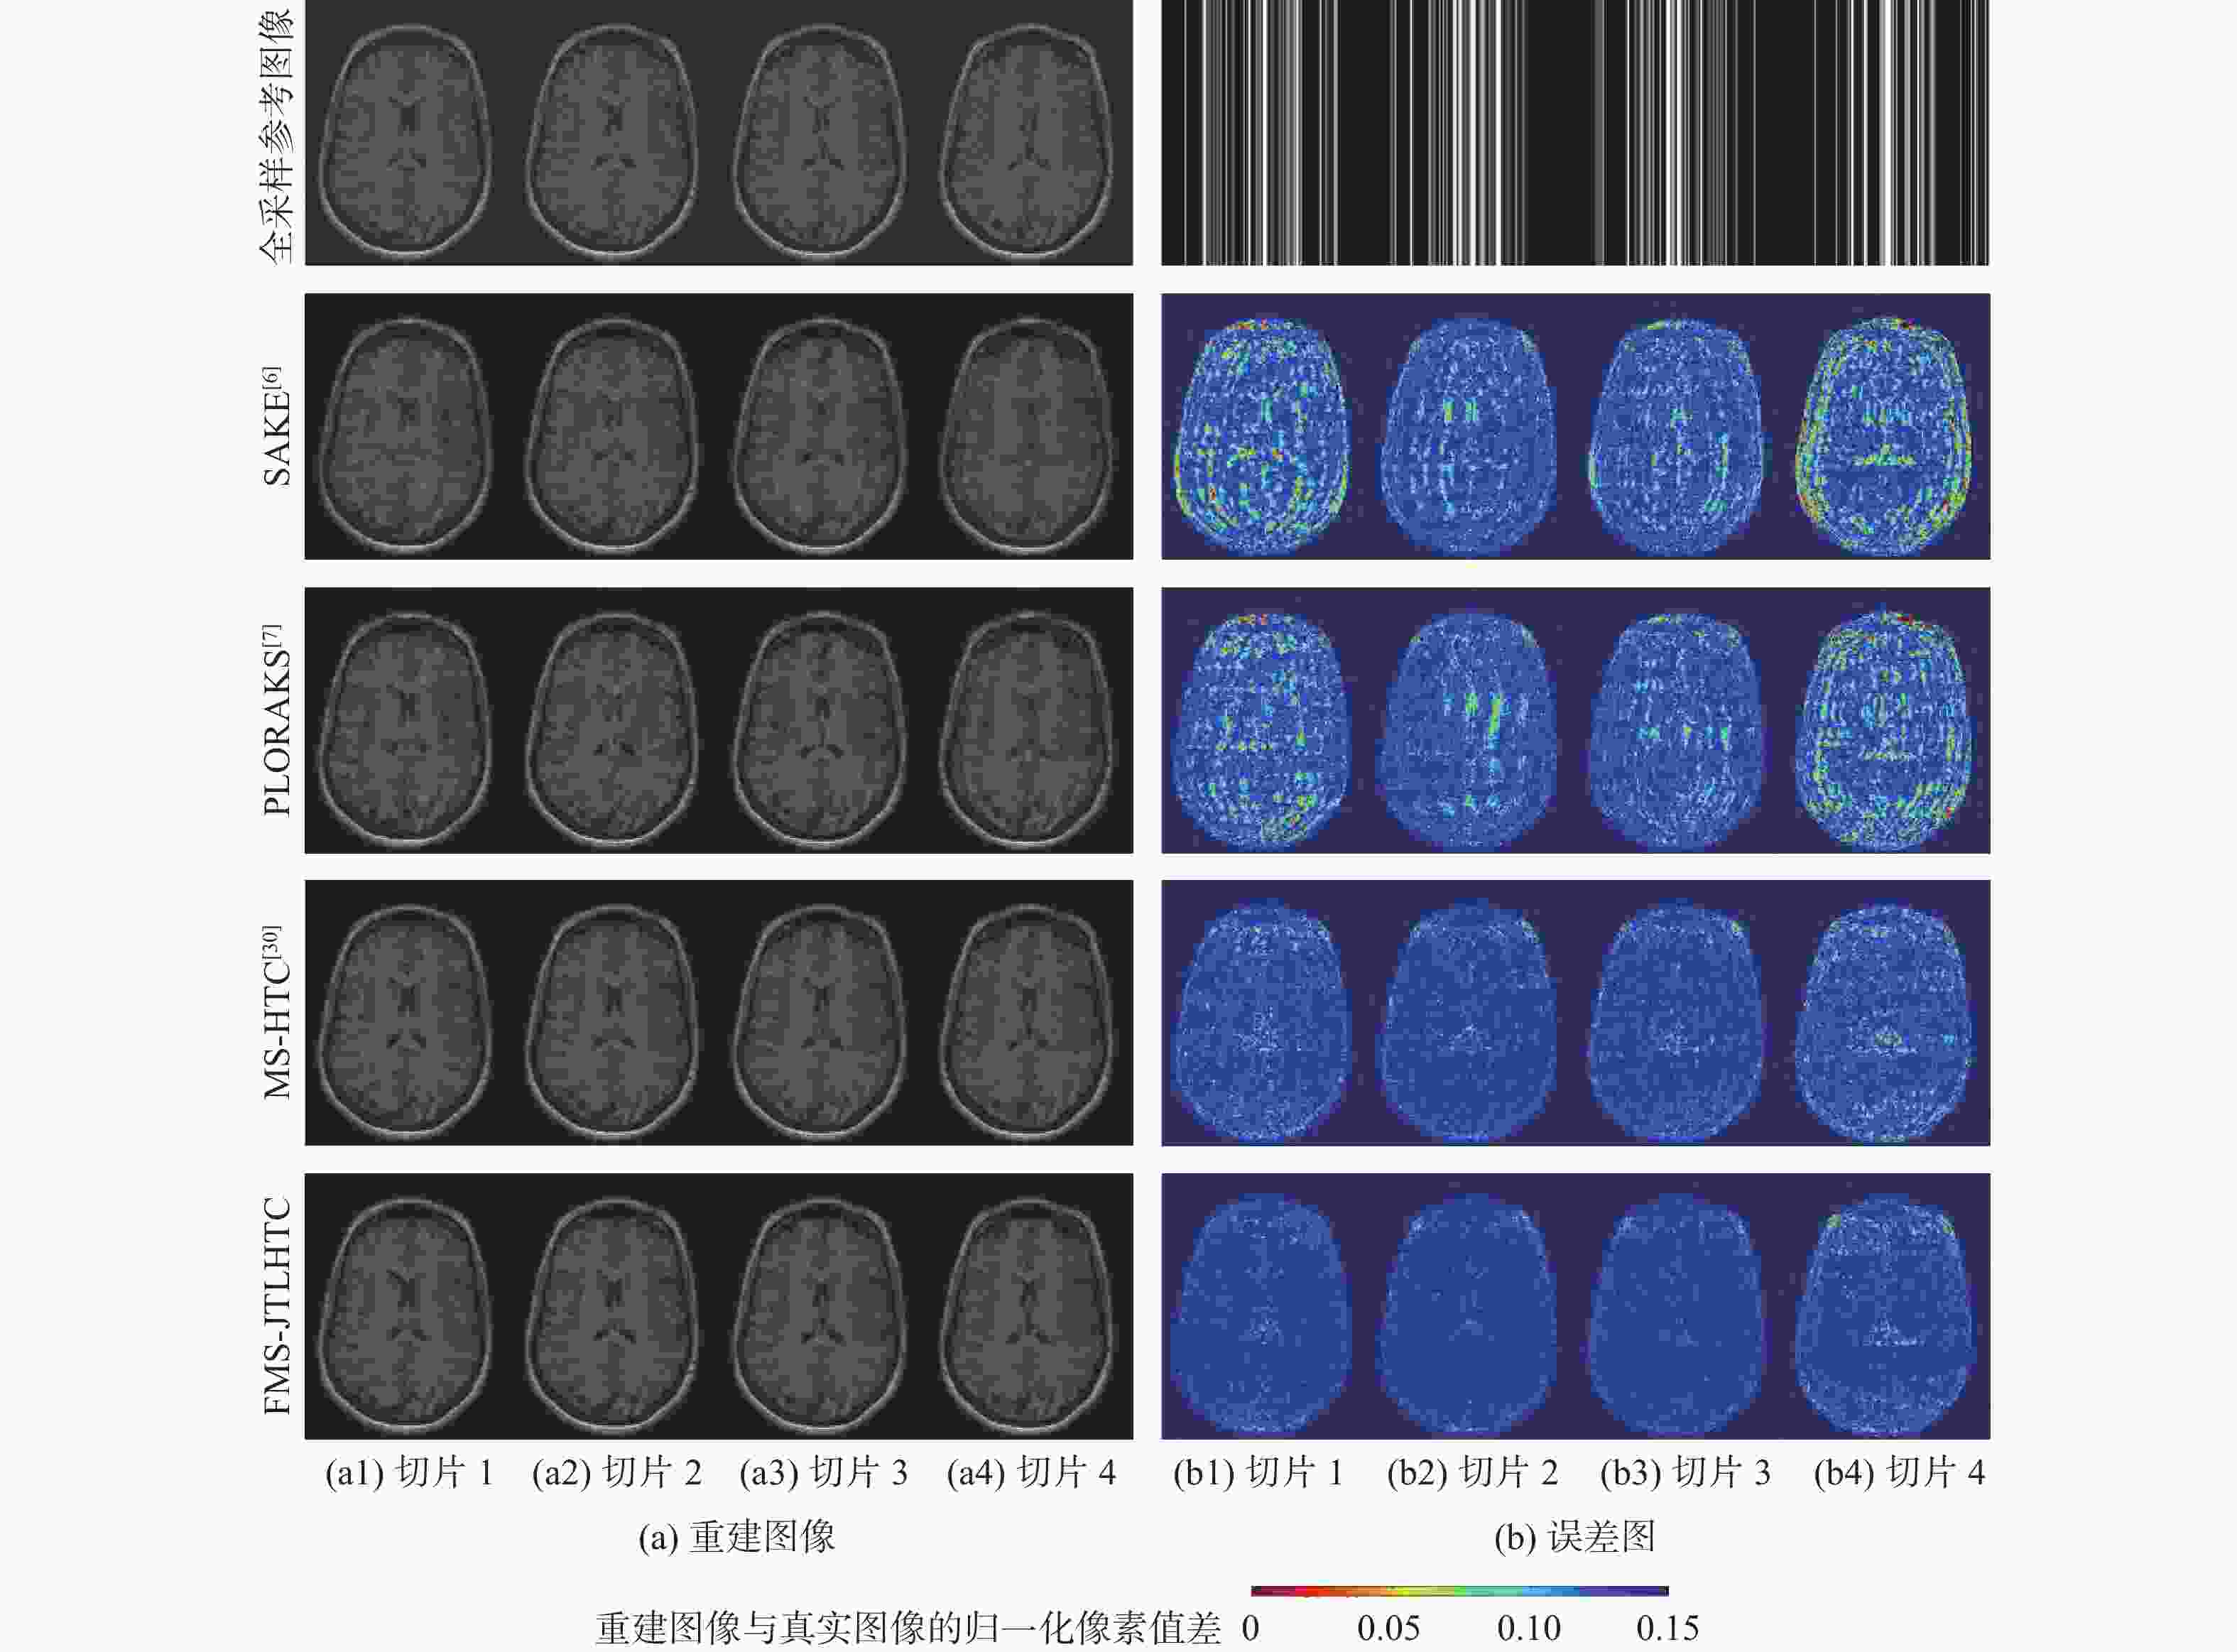

二维(2D)多切片磁共振数据在相邻切片之间具有高度的相关性,通过利用切片间的冗余性能够重建出更高质量的切片图像,但由于硬件条件的限制,2D多切片磁共振成像(MRI)需要耗费大量时间。为提高2D多切片磁共振图像的重建质量和重建速度,将联合稀疏变换学习正则项引入到多切片Hankel张量完成(MS-HTC)模型中,提出一种快速2D多切片磁共振成像重建(FMS-JTLHTC)算法。该算法使用交替方向乘子法对目标问题进行求解;引入快速迭代收缩阈值法加快收敛,并使用图形处理器对算法进行加速。使用4组脑部数据集在2种不同采样模式下进行实验,结果表明:FMS-JTLHTC算法的峰值信噪比(PSNR)相较于同时自动校准和K空间估计(SAKE)算法、并行成像数据的局部K空间领域的低秩建模(PLORAKS)算法和MS-HTC算法分别平均提高了4.04 dB、3.67 dB和2.07 dB,而且重建速度相比MS-HTC算法提高了14倍。

Abstract:Due to the significant correlation between neighboring slices in two-dimensional (2D) multi-slice magnetic resonance data, higher quality slice pictures can be reconstructed by taking use of the redundancy between slices. However, 2D multi-slice magnetic resonance imaging requires an amount of time. To improve the reconstruction quality and speed of 2D multi-slice (MRI) images, proposes a fast 2D multi-slice MRI reconstruction (FMS-JTLHTC) algorithm, which introduces the joint transform learning regular term into the multi-slice hankel tensor completion (MS-HTC) model. Prior to introducing the fast iterative shrinkage-thresholding procedure to accelerate convergence and utilize the graphics processing unit to speed up the procedure, the alternating direction method of multipliers is used to solve the objective issue. Experiments using four brain datasets in two different sampling modes show that the peak signal-to-noise ratio (PSNR) of the FMS-JTLHTC algorithm is improved by an average of 4.04 dB, 3.67 dB, and 2.07 dB compared to the simultaneous atuo-calibrating and K-space estimation (SAKE), low-rank modeling of local K-space neighborhoods with parallel imaging data (PLORAKS) and MS-HTC algorithms, respectively, the reconstruction speed is improved by a factor of 14 compared to the MS-HTC algorithm.